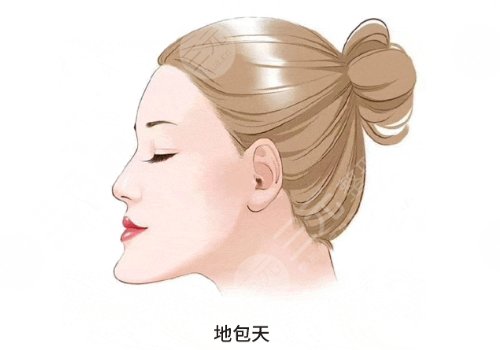

上高中的时候已经知道自己有着很严重的牙和畸形情况,明明五官并不算难看,但是凑到一起总感觉说不出的别扭,下巴多出一截严重的地包天让我感到很自卑,这个问题成为了多年以来心中的烦恼。工作之后积攒了一定的积蓄,就决定去做正颌手术,查询了很多医院之后发现北京世纪坛医院整形美容外科。当中的正核技术比较精湛,于是满心期待的到医院进行了面诊。